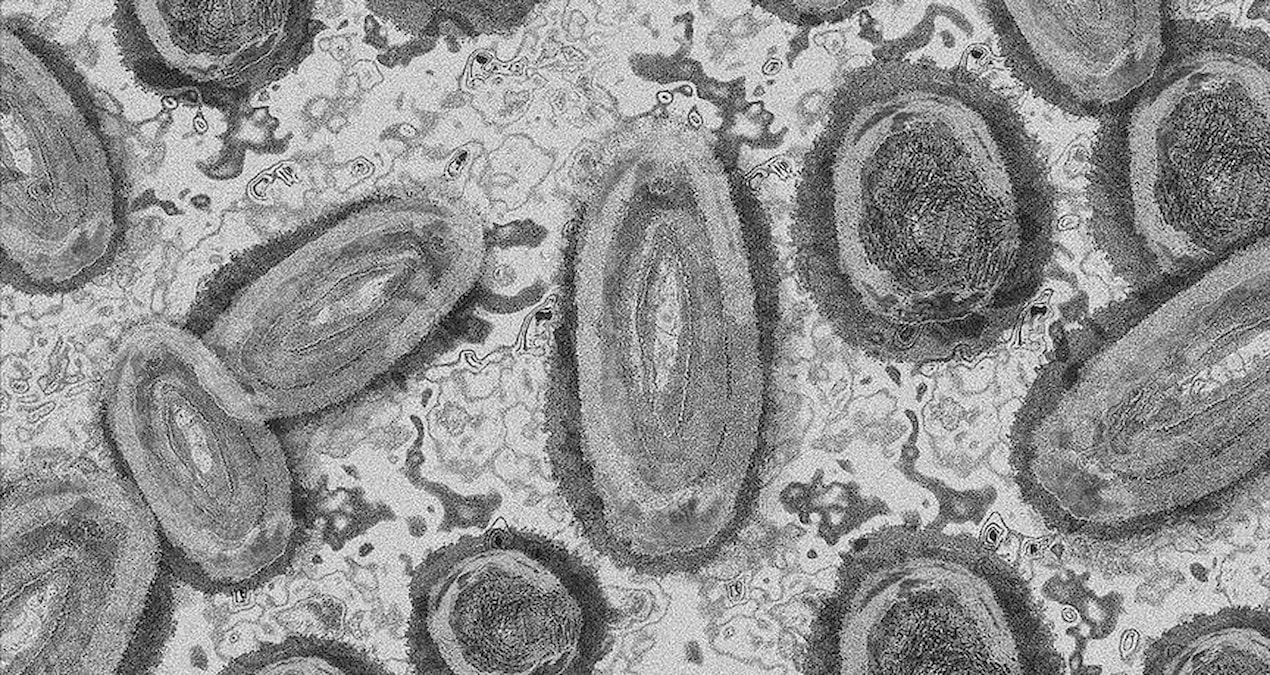

Kongo Demokratik Cumhuriyeti’nin Kuzey-Kivu eyaletinde, 8 M çiçeği vakası tespit edildiği bildirildi. DSÖ virüs hakkında uyarı yaparken Güney Afrika’da da M çiçeği dolayısıyla üçüncü ölüm gerçekleşti.

Kongo’nun Kuzey-Kivu Valiliği’nden yapılan açıklamada, eyaletin Nyiragongo ve Goma şehirlerinde toplam 8 M çiçeği (Mpox) vakasının tespit edildiği duyuruldu.

Hastalığın, bulaşıcı ve tehlikeli olduğu vurgulanan açıklamada, “M çiçeğinin sadece tespit edilen şehirler için değil tüm eyalet için tehdit oluşturduğu” uyarısı yapıldı.

Kongo Demokratik Cumhuriyeti Sağlık Bakanlığından 5 Haziran’da yapılan açıklamada ise bu yıl 7 bin 396 M çiçeği vakasının görüldüğü, salgın nedeniyle 371 kişinin hayatını kaybettiği bildirilmişti.

Ülkede geçen yıl 654’ü ölümle sonuçlanan 14 bin 626 M çiçeği vakası tespit edilmişti.